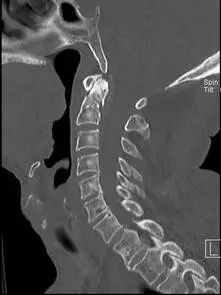

经过全程监护和系统治疗,患者术后恢复良好,骨折解剖复位,复查X线及CT显示固定位置佳,术后3天下地行走,术后4天即出院回家休养。

该手术为我市首例完成C1、2椎弓根钉棒系统固定手术,填补了枣庄在上颈椎外伤手术史上的空白,展现了枣庄市立医院脊柱外科不怕困难、勇于突破、积极向上的精神面貌,也是王存平主任技术高超、胆大心细的具体体现。